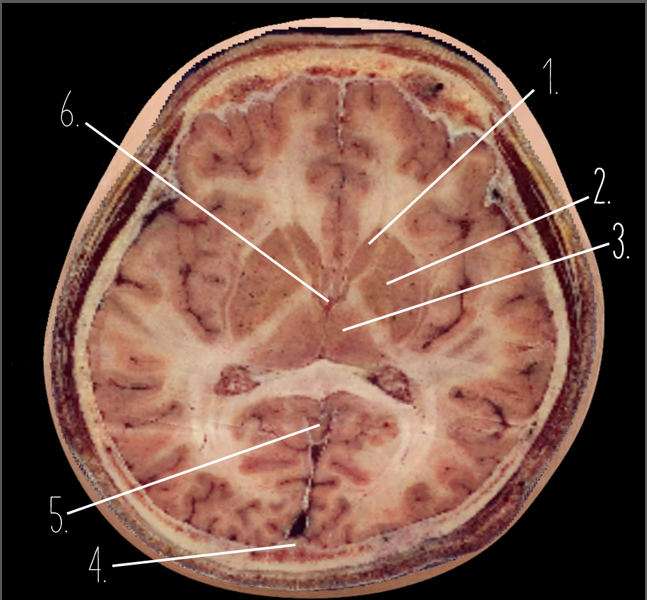

1?

Choroid Plexus

2?

Lateral Ventricle

3?

Caudate Nucleus

4?

Third Ventricle

5?

Parietal Bone

6?

Occipital Bone

7?

Falx Cerebri